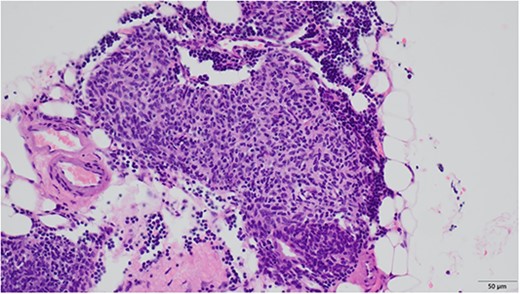

Microscopic findings revealed nodular hyperplasia of the thymic epithelium with a diameter of 400 μm.